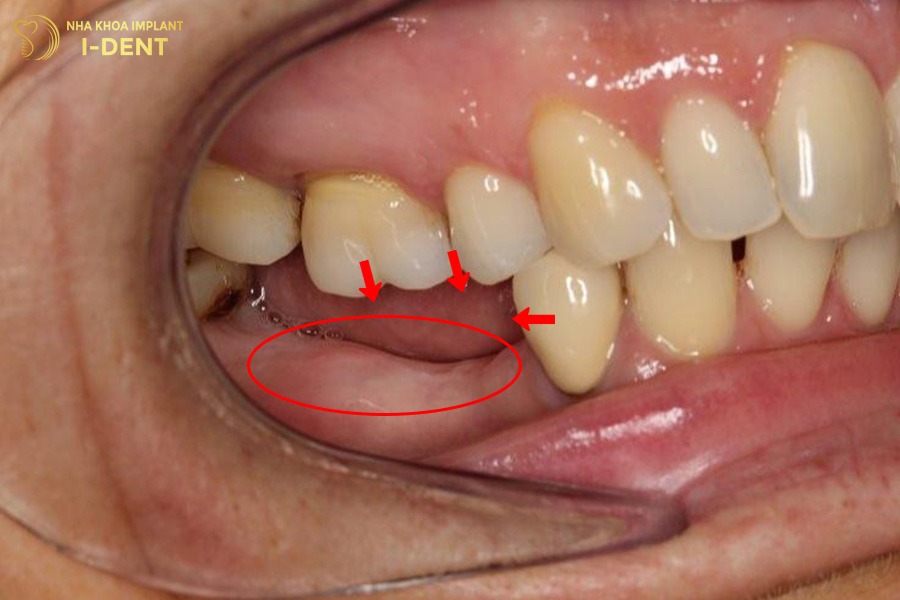

- Mất răng lâu ngày khiến các răng lân cận bị xô lệch, trồi răng hoặc đổ trục.

- Xương ổ răng tại vị trí mất răng bị tiêu biến làm giảm khả năng nâng đỡ răng.

- Viêm nha chu mãn tính, sâu răng hoặc sang chấn khớp cắn kéo dài khiến toàn bộ hàm răng yếu đi.

Mất răng lâu năm khiến các răng lân cận bị xô lệch, trồi răng.